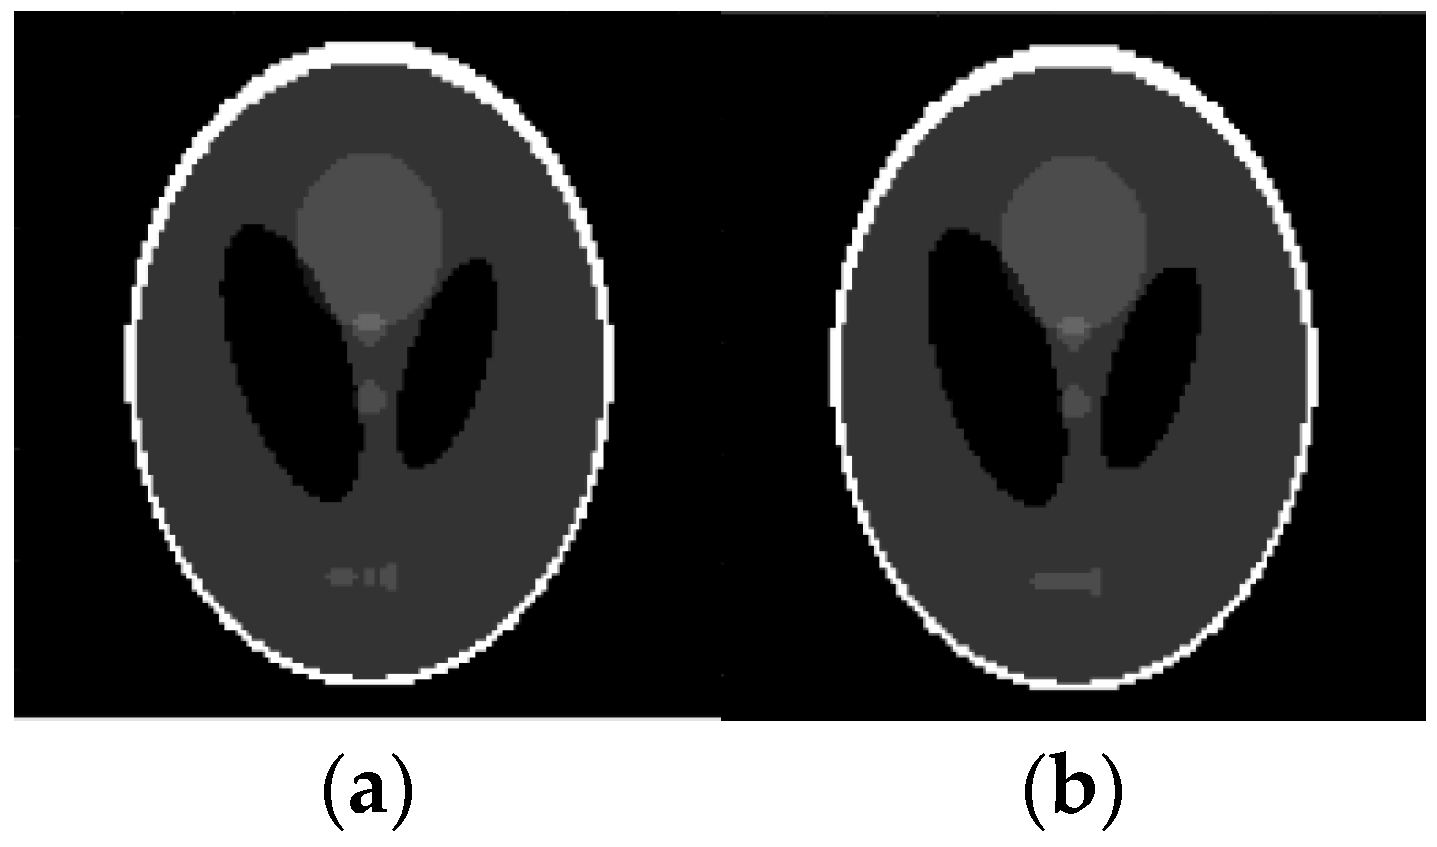

4.1. Reconstruction of Binary Images

4.2. Reconstruction of Gray Scale Images